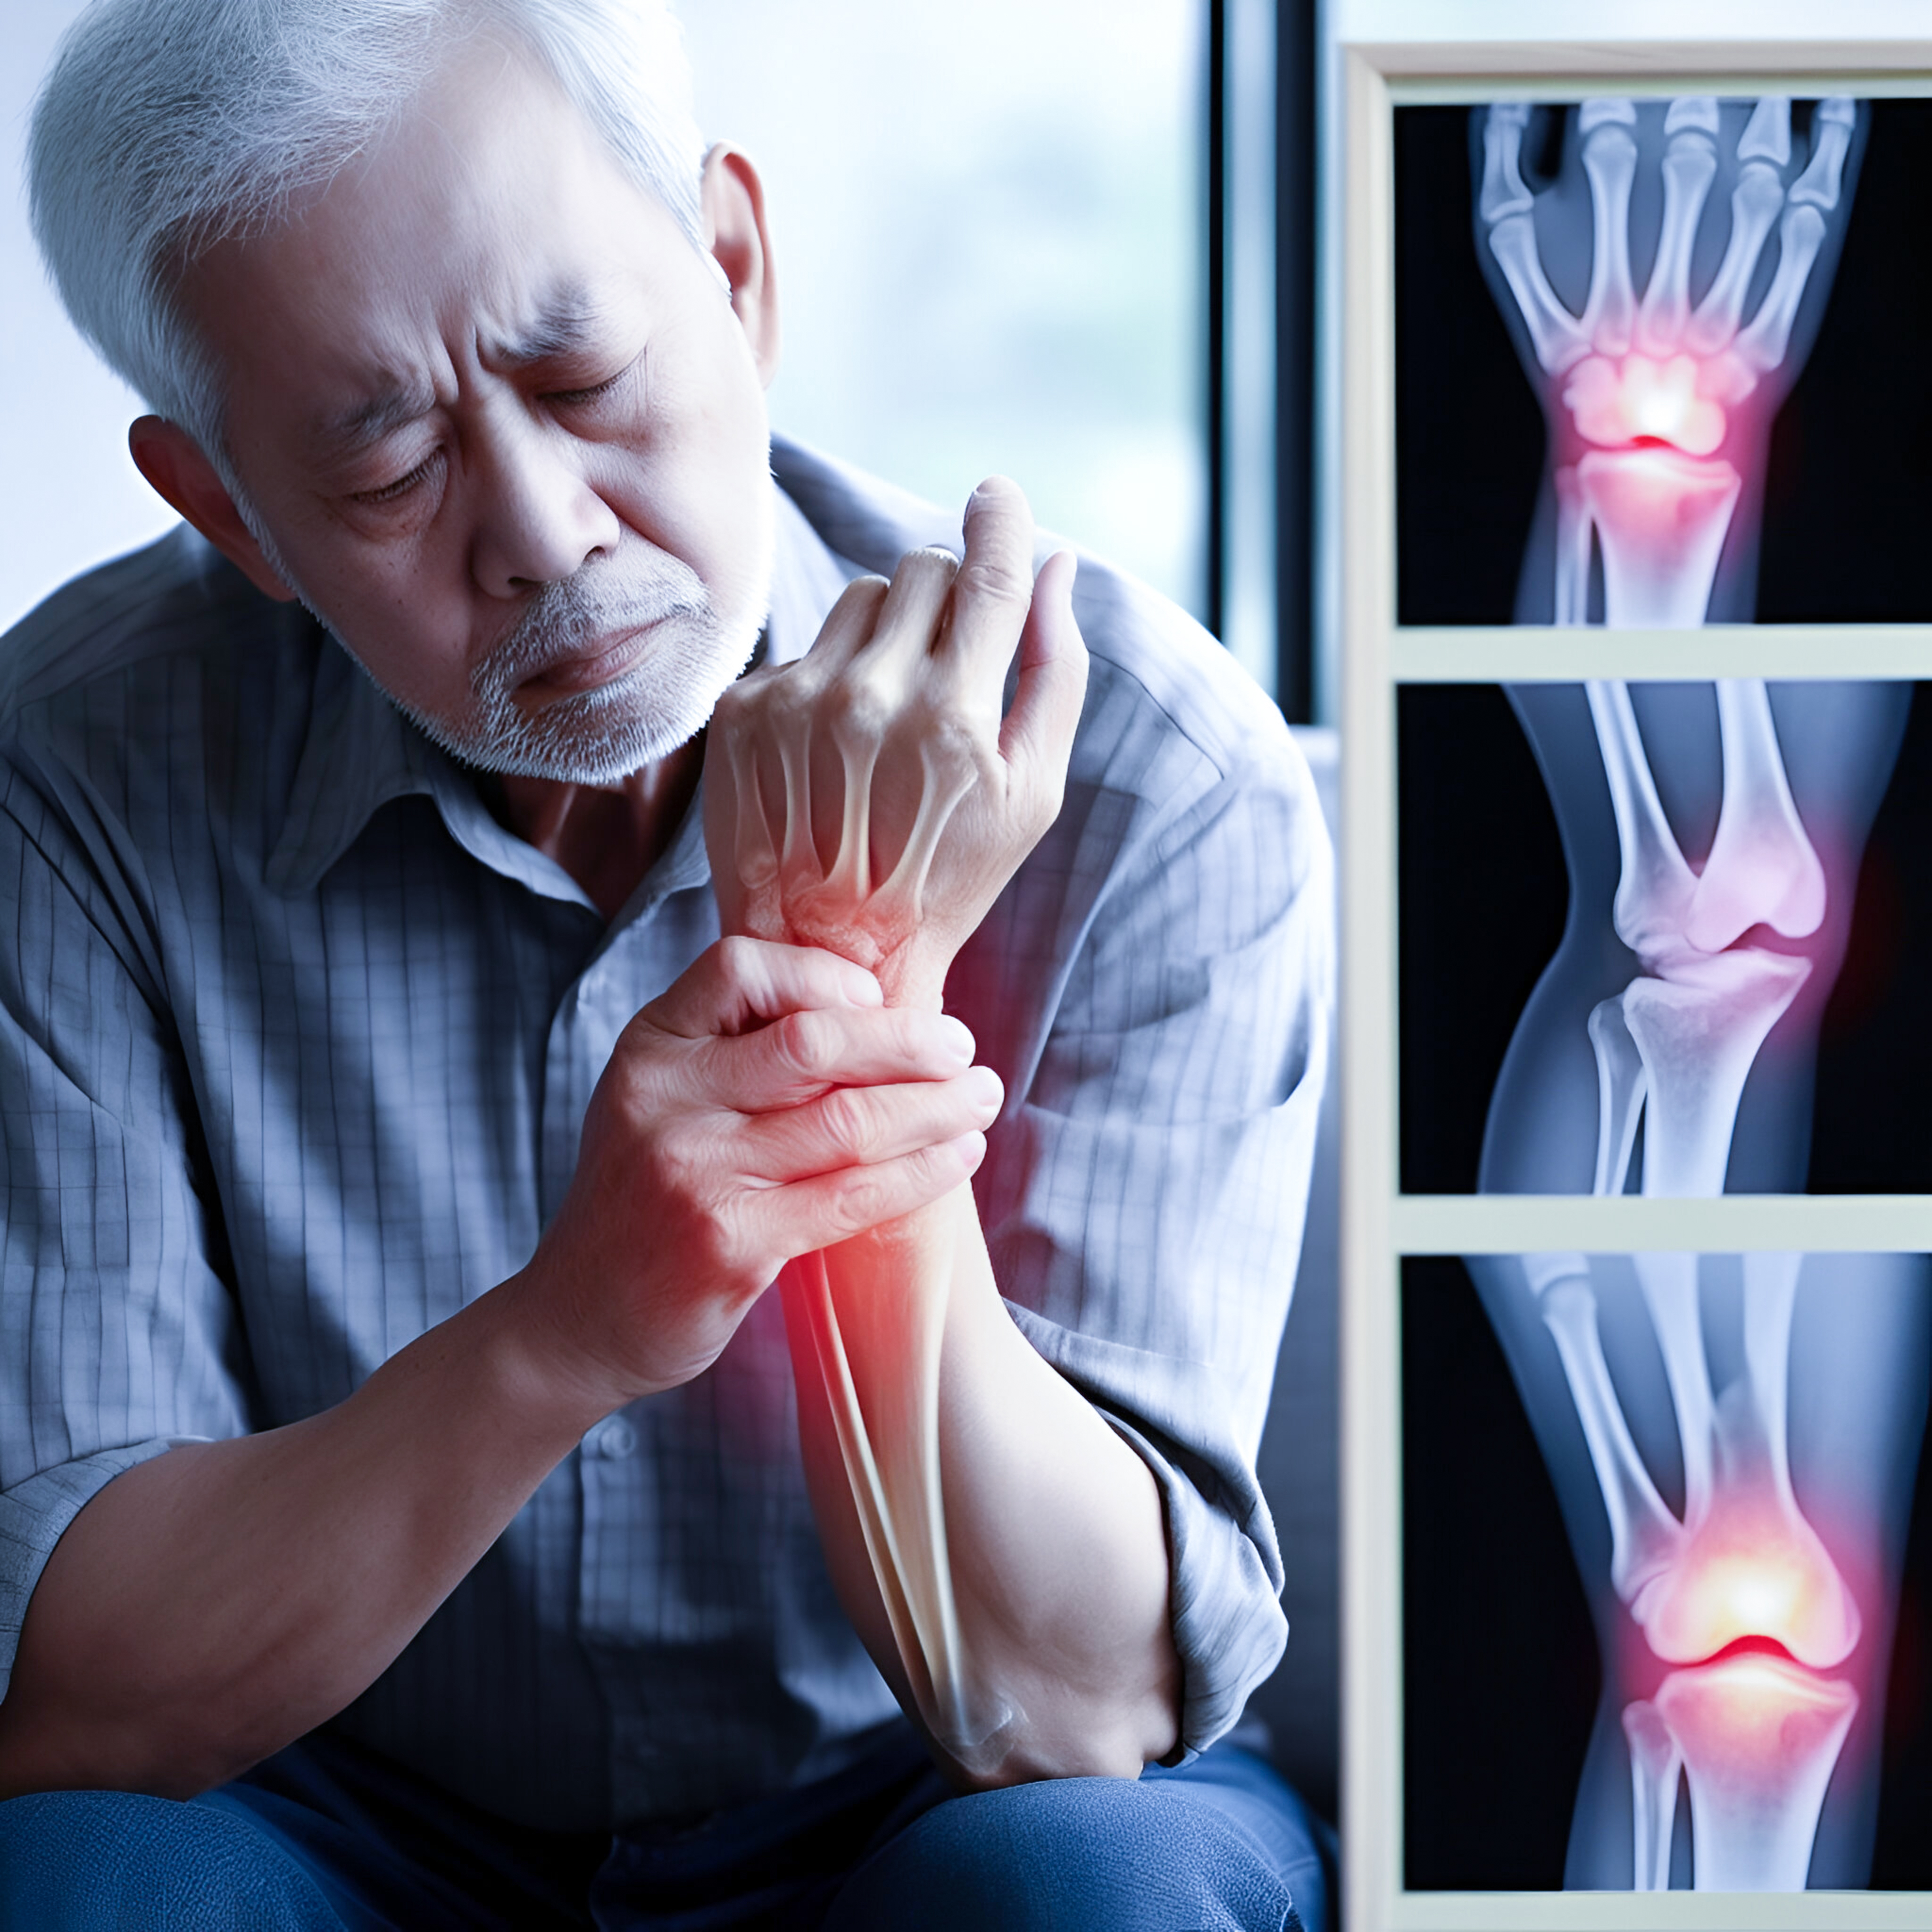

Inflammation is a key aspect of the body’s immune defenses. It can be acute or chronic. Symptoms can include swelling, heat, pain, and more. Treatments can depend on the underlying cause.

Experts believe inflammation may contribute to a wide range of chronic diseases. Examples of these are metabolic syndrome, which includes type 2 diabetes, heart disease, and obesity.

People with these conditions often have higher levels of inflammatory markers in their bodies.